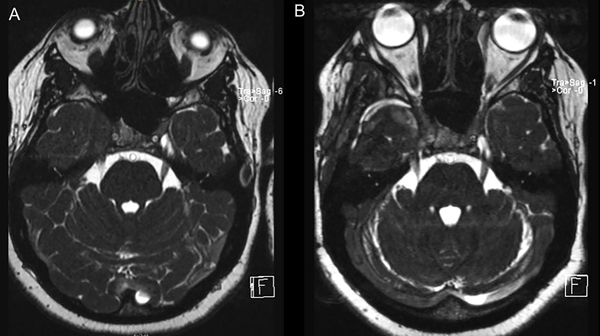

La anatomía patológica informó lesión compatible con pseudotumor inflamatorio. Realizó un mes de tratamiento con corticoides. Se realizó RMN de control a los 2 meses en la que se evidenció importante reducción del volumen de la lesión (Figura 2 y 3).

Figura 2. RMN de cerebro en secuencia T1 con contraste; cortes axial y coronal (A y B). Control a los 2 meses posterior a la cirugía y corticoterapia.

Figura 3. RMN secuencia CISS preoperatoria (A) y control a los 2 meses (B).

La paciente posteriormente inició corticoides con lo cual mejoraron posteriormente los síntomas. En la RMN postoperatorio (a los 2 meses) se evidenció una marcada reducción de la lesión, objetivando una clara respuesta al tratamiento farmacológico.